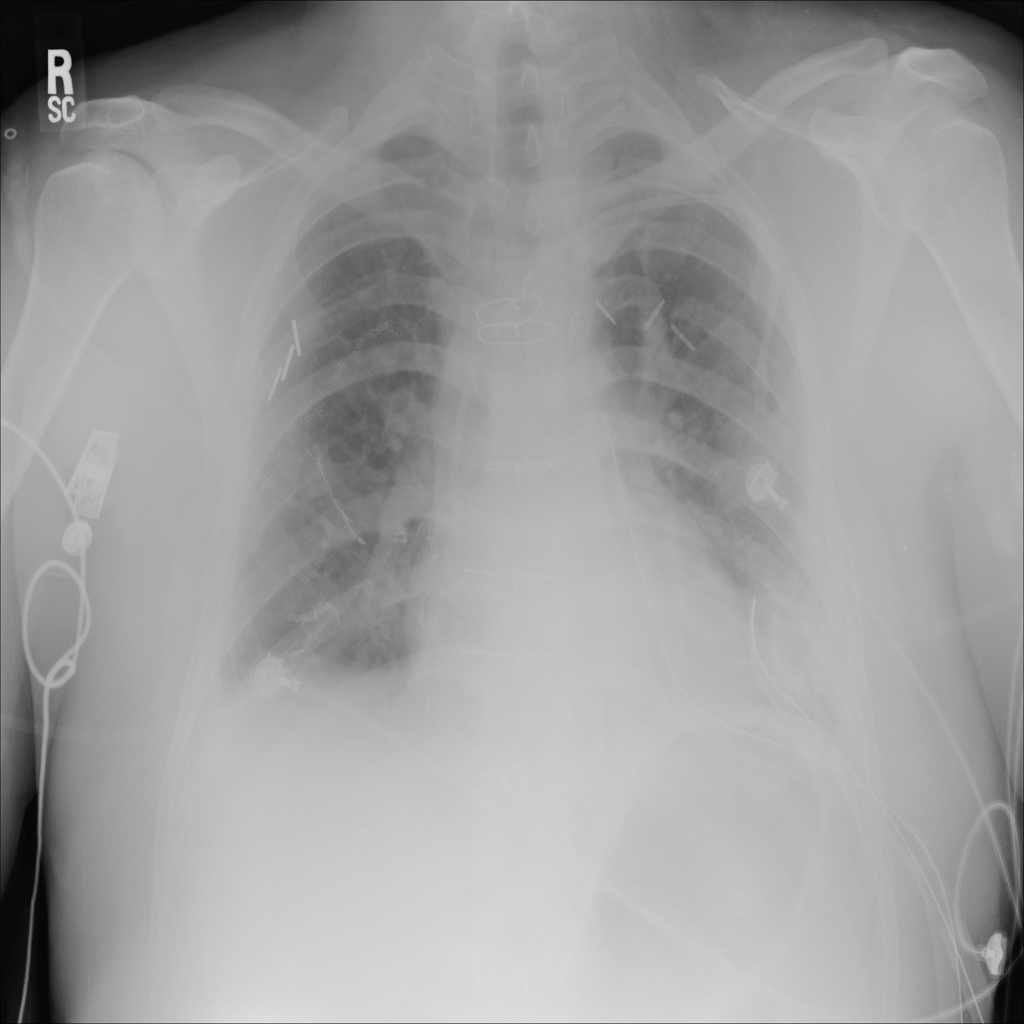

Showing up to 90 reference images for Nodule.

PAT-50E5 · IMG-000Nodule

PAT-50E5 · IMG-000

PA